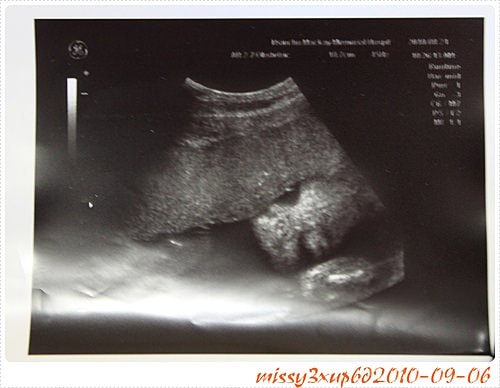

應該說大醫院設備太好了吧,哈哈,當初別說看桓的表情,一點記憶點有什麼都不知道,只知道桓那時候很大辣辣的十五周就開獎了= =。 就是腳開開那種!!! 所以玳瑁在孕期中,超…

這次去馬偕其實是21W了,我才知道原來例行性超音波,會照的這麼仔細喔? 會看一下手呀,腳呀,肚子頭圍,我其實很囧,因為桓兒根本沒有這樣仔細看過。 這叫做傻傻生傻傻沒事嗎? …

其實是有些失落的,因為我真的很想知道性別><。 很想趕快知道是女孩,狂喜一下,也很想趕快知道是男孩,好把期盼買女孩衣服的心思放下。 這次去馬偕算是挺早得,至少中午…